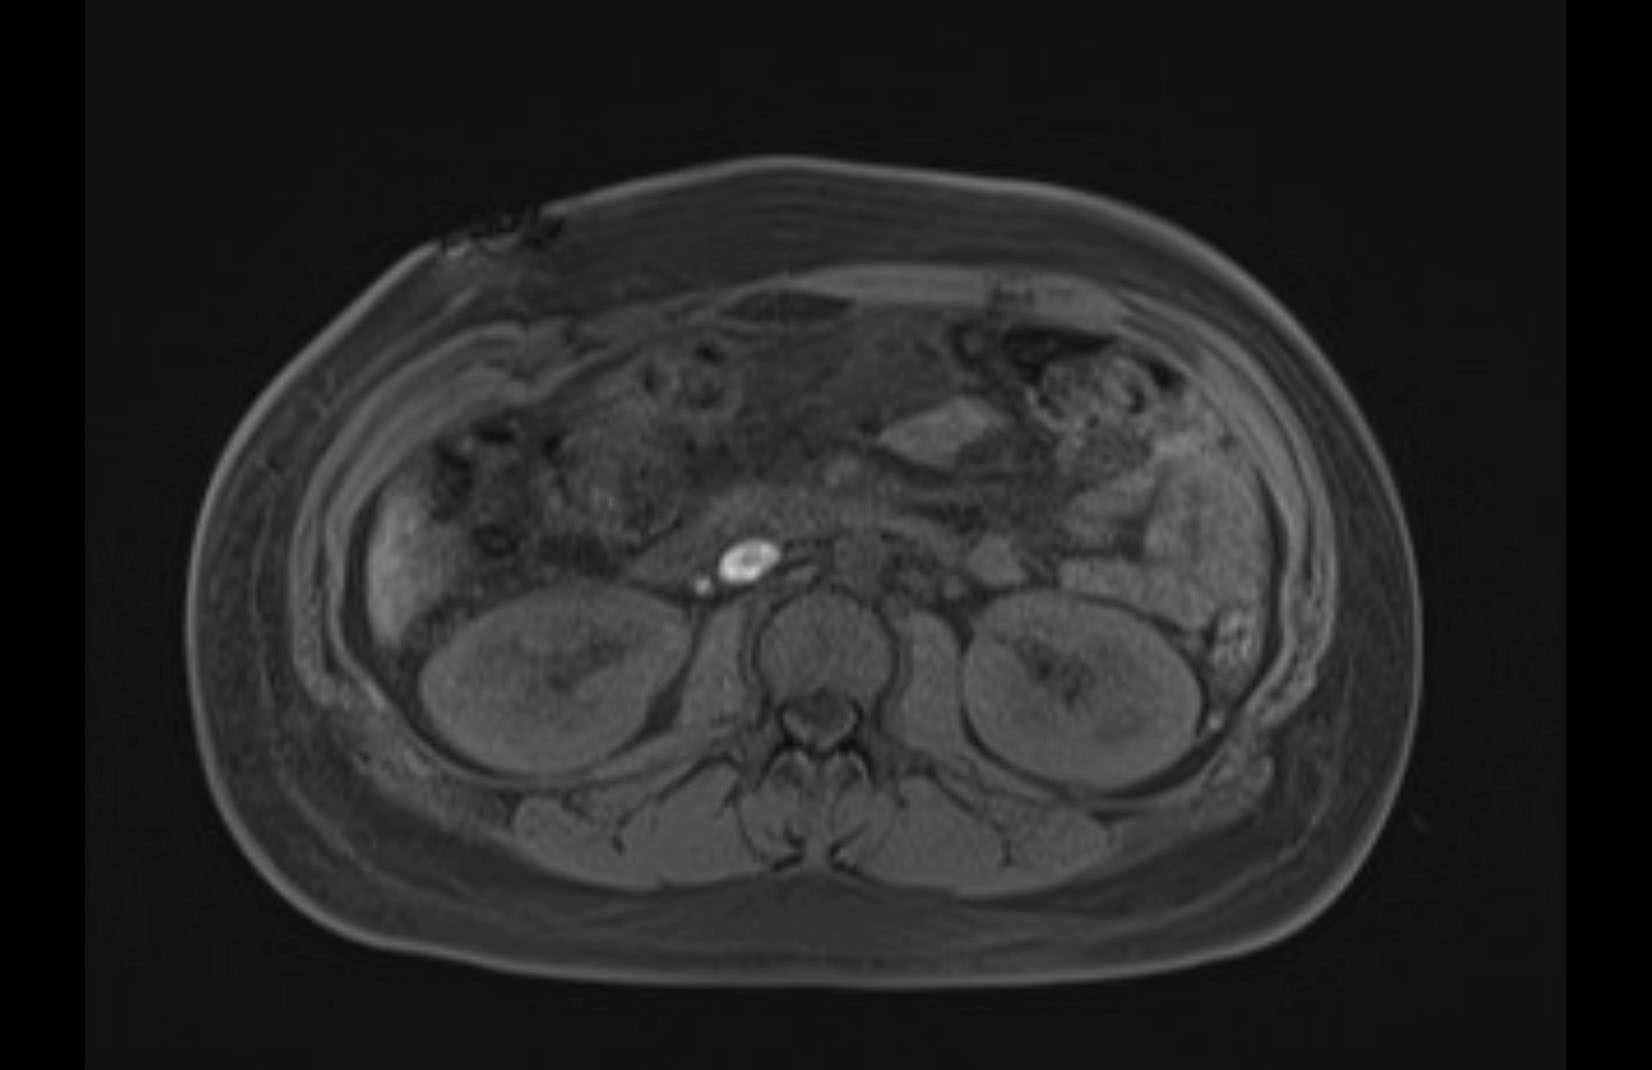

MRI T1

MRI T2